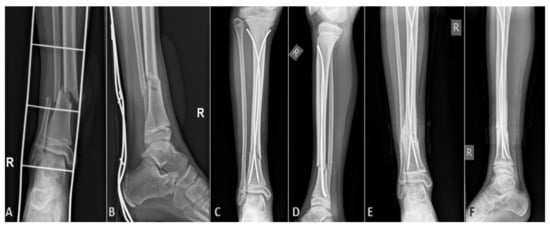

On the first postoperative day, strict rest is required, mostly due to pain control. From the second or third postoperative day (individually, depending on age and other factors, such as general condition of the patient or associated injuries), physical therapy and getting out of bed with crutches begins. After the patient learns to walk stably using crutches, if the other parameters are satisfactory, the patient is discharged to home care, continued with ambulatory physical therapy after discharge. For the first three or four weeks, the patient does not step on the operated leg, and then, after radiological verification of the fracture, begins gradual weight bearing. For the first few days, the bearing is approximately one-seventh of the body weight, after which the bearing gradually increases. On average, after 8 to 10 weeks of osteosynthesis, after radiologically verifying a good callus, a crutch-free gait begins. Each patient underwent an intraoperative X-ray after repositioning the bone fragments and placing of titanium elastic nails. Control X-rays were taken seven days after the procedure, and after one, three, and six months, or until healing of the bone was completed (Figure 1). Radiological evaluation was carried out using standard AP and LL radiographs at each visit to evaluate the consolidation of the fracture and identify complications such as secondary displacement, shortening, nail migration, delayed union, nonunion or malunion, and re-fracture (Figure 2). Nonunion was defined as the lack of appropriate healing within six months from index surgery. Malunion was defined as angular deformity of greater than 5–10° (depending on patient’s age) in the coronal or sagittal plane. Limb length inequality >1 cm was considered as limb shortening. All nails were removed under general anesthesia when the radiological healing was evident at the median of six months.

Figure 1. Displaced tibial shaft fracture in 11-year-old female patient: (A) preoperative AP radiograph; (B) preoperative LL radiograph; (C) AP radiograph one month after surgery; (D) LL radiograph one month after surgery; (E) AP radiograph three months after surgery; (F) LL radiograph three months after surgery.